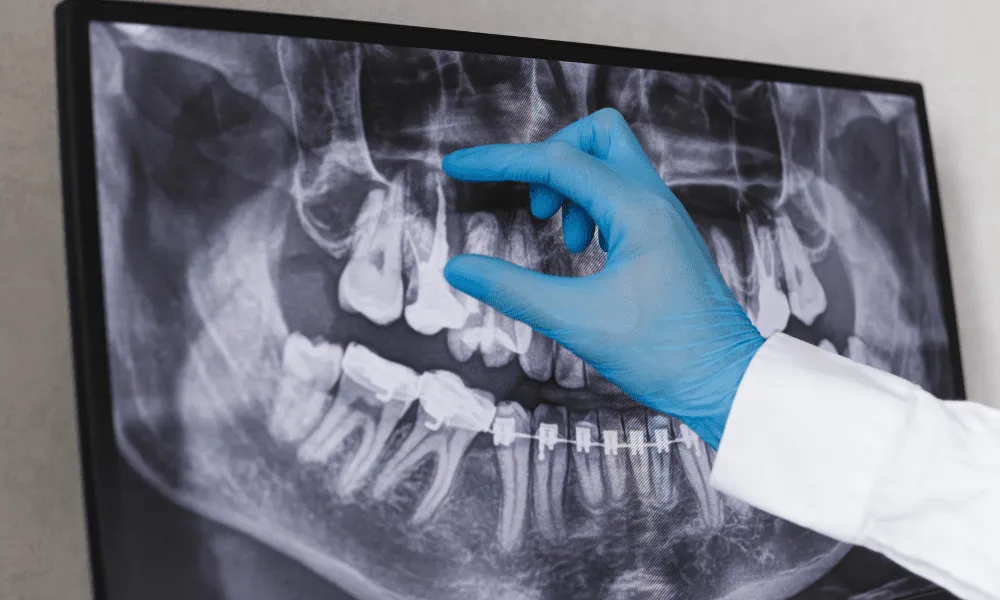

Root canal X-rays are vital tools for dentists. They provide a clear, detailed view of the areas of your teeth and gums that can’t be seen during a standard dental checkup. Let’s break down how root canal X-rays help in different situations:

By providing these crucial insights, root canal X-rays help dentists diagnose problems accurately and choose the best treatments to keep your teeth and gums healthy.